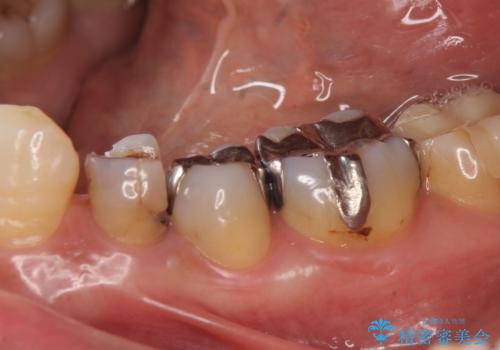

- 左下の詰め物が取れてしまったので治療したい、ついでに銀歯も白くしたいといらっしゃった方の症例です。

銀歯及び虫歯を除去後、オールセラミッククラウンによる補綴を行いました。